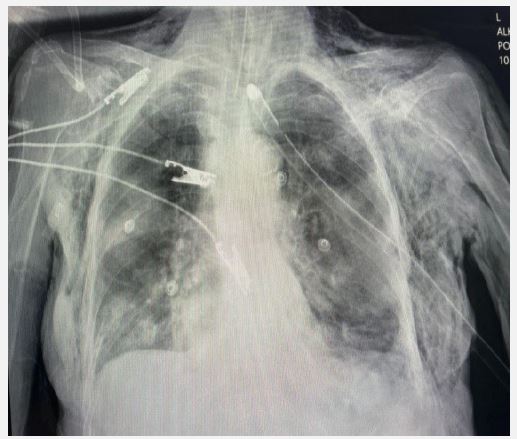

The patient was diagnosed with septic shock secondary to pneumonia and UTI. Management included broad-spectrum antibiotics, intravenous hydration, and vasopressor support for persistent hypotension. A left subclavian central venous catheter insertion for vasopressor administration was attempted but complicated by significant bilateral subcutaneous emphysema, though no pneumothorax was identified. A chest tube was inserted to manage the emphysema, with a post-procedure chest X-ray confirming appropriate placement (Figure 1). Over the next 48 hours, the subcutaneous emphysema resolved, but the patient’s hypotension persisted, and her clinical condition worsened. Despite intensive care measures, the patient succumbed to her illness after two days.